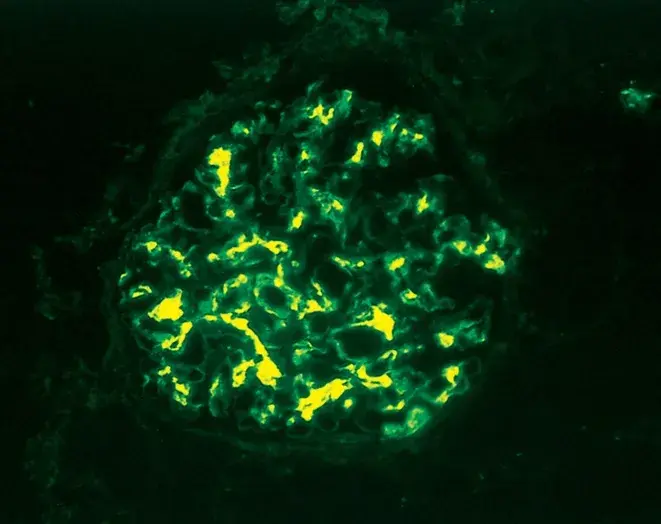

Diálise Peritoneal na Doença Renal Policística: existe algum motivo para não indicar?

Diálise Peritoneal na Doença Renal Policística: existe algum motivo para não indicar?

A DRPAD não é contraindicação à DP — e, na prática, muitos pacientes têm resultados comparáveis à hemodiálise. O “porém” está na mecânica: rins/hepatomegalia podem reduzir tolerância a volumes, aumentar risco de hérnias e extravasamentos, e piorar desconforto respiratório. Com técnica adequada (cateter presternal ou lateral, volumes menores, cicladora noturna e decúbito supino), a maioria das barreiras é contornável. Neste post, revisamos quando a DP é ótima, quando exigir cautela e como ajustar a prescrição para segurança e qualidade de vida.